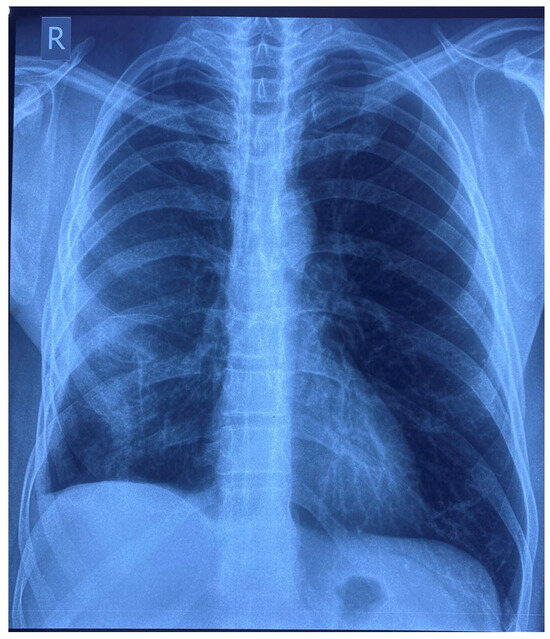

On the seventh day of hospitalization, the patient’s condition worsened and he began to exhibit chest pain, recurrence of fever after 4 days of being afebrile, and right basal subcrepitant rales. A chest X-ray was performed, which showed an inhomogeneous opacity (3.8/3.7 cm) on the lower right lobe and a residual inhomogeneous opacity on the upper left lobe (Figure 1). Biological tests showed leukocytosis (31.910 cells/mm3) with neutrophilia (81.3%) and lymphopenia (7%), an inflammatory syndrome (erythrocyte sedimentation rate (ESR) = 27 mm/1 h, fibrinogen = 507 mg/dL, procalcitonin = 12.27 ng/mL), a syndrome of nitrogen retention (creatinine = 1.91 mg/dL, urea = 107 mg/dL), and a CD4 count = 395 cells/mm3. The patient received antibiotic treatment with Meropenem 1 g/12 h (empirical treatment for bacterial suprainfection; creatinine clearance = 48 mL/min) and the initial antiretroviral therapy was replaced with Bictegravir/Emtricitabine/Tenofovir Alafenamide (for regimen simplification).

Figure 1. Chest X-ray (day 7).